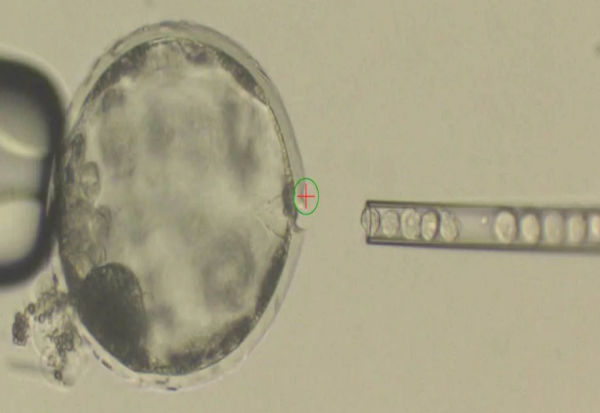

Фото: Juan Carlos Izpisua Belmonte, The Salk Institute

Во новите известувања научниците наведуваат дека органоидите преживеале одреден период (во еден случај два месеца) и дури и се поврзале со циркулаторниот и нервниот систем на животните од лабораторијата, пренесувајќи крв и нервни сигнали преку животното-домаќин и всадените човечки клетки. Ова е невиден напредок во истражувањата на мини-мозоците.

Тоа што мини-мозоците можат да бидат израснати во лабораториите е голем напредок бидејќи тие имаат многу исти карактеристики како и човечките мозоци кога се во рана развојна фаза. Иако не се „живи“ во иста смисла на која сме ние, тие растат и дури и можат да реагираат на сличен начин на стимуланси како психоделични дроги. Органоидите најверојатно ќе направат револуција во истражувањето на човечкиот мозок бидејќи научниците можат да извршат тестирања врз нив кои не би било етички да пробаат да ги вршат врз живи луѓе.